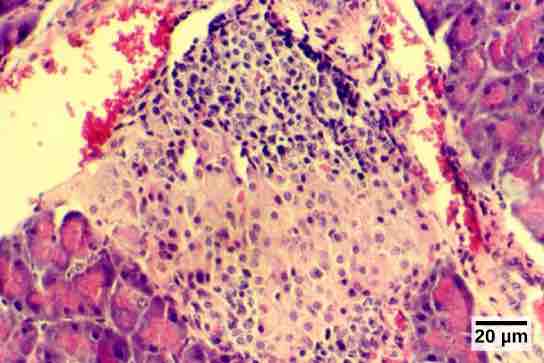

Islets of Langerhans

The islets of Langerhans are clusters of endocrine cells found in the pancreas; they stain lighter than surrounding cells. The alpha and beta cells produce glucagon and insulin, respectively.